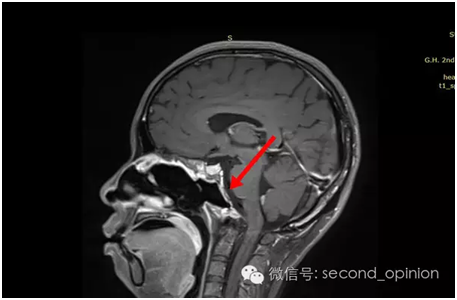

质子治疗后第一次复查

质子治疗后第二次复查

质子治疗后第三次复查

2015年1月25日 对比质子治疗之前增强核磁共振影像无明显变化,脊索瘤放疗后变化缓慢,建议3月后继续复查。

2015年04月01日 对比增强核磁共振影像,同第一次复查。

2015年06月03日 对比增强核磁共振影像,对比第三次复查,肿瘤略有缩小。